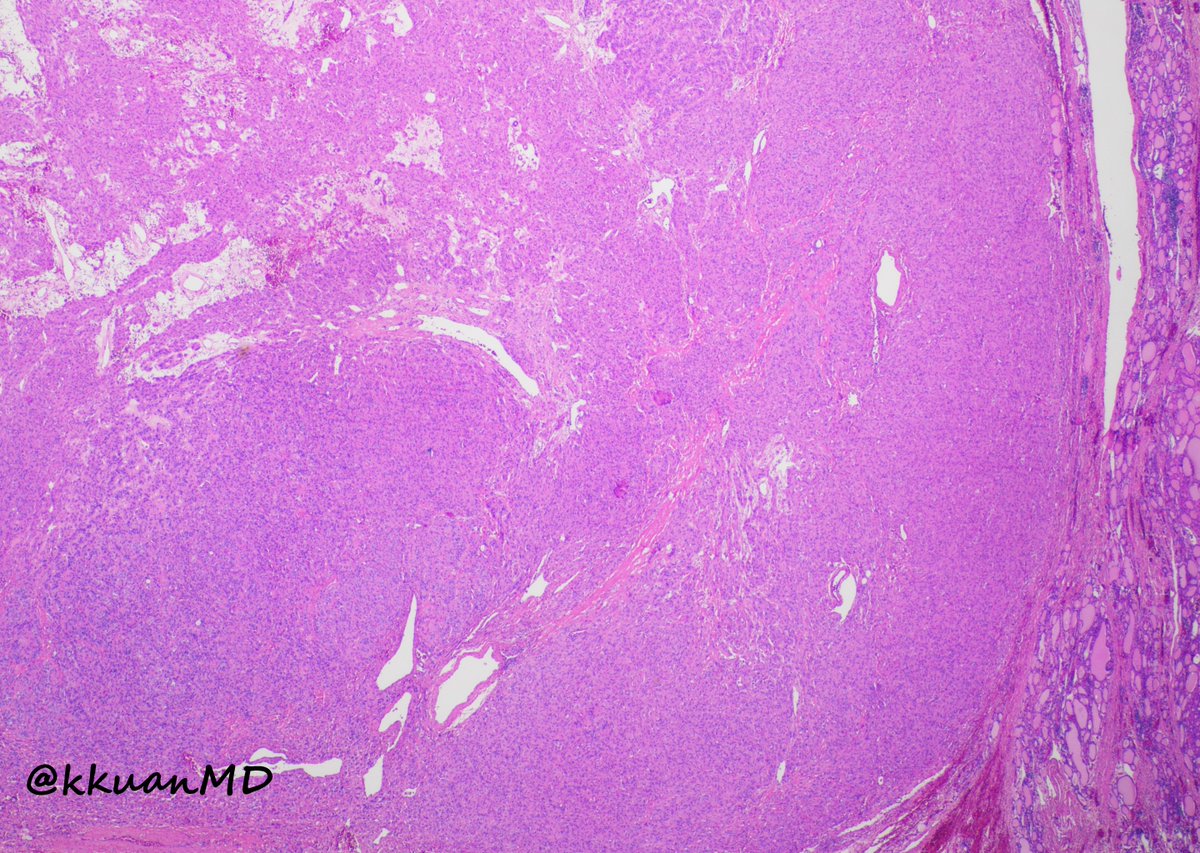

@kkuanMD

Kevin Kuan

4 years

9

67

134